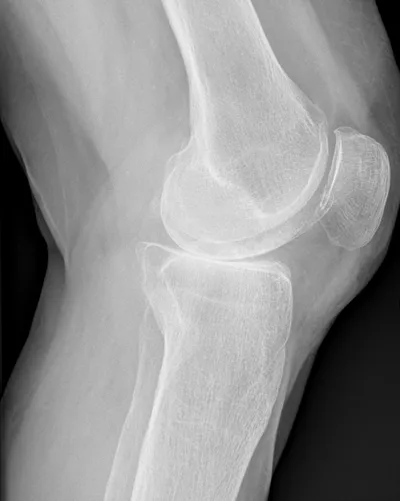

Patellar tendinosis with tear

MRIKneeSagittal+3

4/23/2026